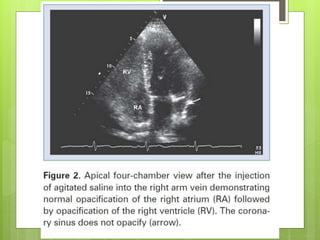

Figure 2. A partial coronary sinus defect beyond the range of the interatrial septum and an

intact flap valve of the oval fossa with its muscular rims were revealed simultaneously at

≈140° section by transesophageal echocardiography (left).

Huang X Circulation 2007;116:e373-e373